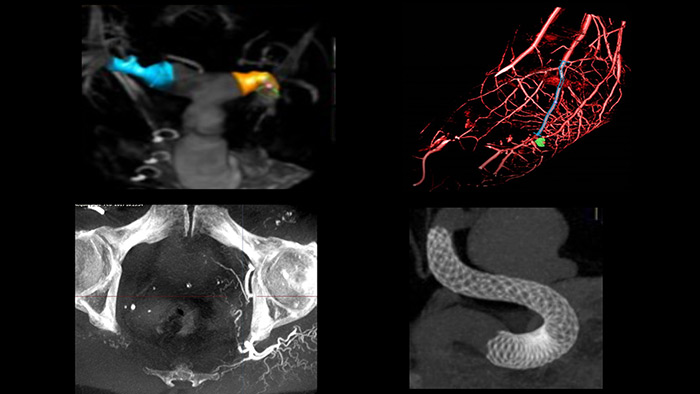

Na sala integrada de hemodinâmica Azurion, as equipe de radiologia intervencionista podem acessar com facilidade as medições e visualizações avançadas em 3D do SmartCT* e o diagnóstico por imagem intravascular (IVUS) do IntraSight em uma tela sensível ao toque ao lado da mesa, economizando tempo e aumentando a confiança clínica.

O SmartCT* fornece imagens semelhantes às da tomografia computadorizada, permitindo que você realize medições avançadas e obtenha visualizações na tela sensível ao toque ao lado da mesa para estudar o tipo e a extensão da doença nos mínimos detalhes. As imagens 3D do SmartCT* podem ajudar a revelar informações que não ficam aparentes em imagens 2D ou de DSA. Essas informações adicionais podem alterar o diagnóstico, o planejamento do tratamento ou a ministração do tratamento, favorecendo melhores desfechos para o paciente.17-19